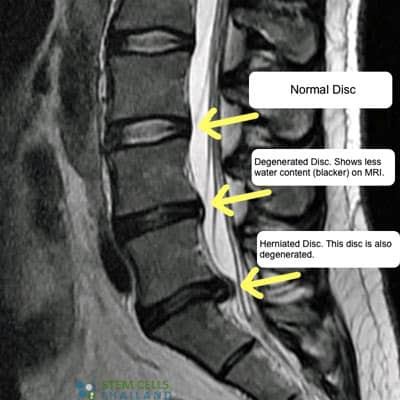

Diagnosing DDD Spinal Stenosis

To diagnose DDD and cervical degenerative disc disease, an orthopedic doctor examines the patient medical history and performs a physical examination. An MRI scan is often needed to identify areas of damage but for patients

stem-cells-spinal-stenosiswho are unable to have MRI Scans a computed tomography (CT) scan can be used to identify vacuum phenomenon, slippage of discs, cracks/defects in the bone structure or damage to soft tissue structures inside the spine. Our functional medical team can also use Radiology scans can also help identify spondylolisthesis (slippage) in surrounding discs so that patient can be graded and offered treatment depending on the scale and severity of the vertebra degeneration.

Degeneration of the spinal discs can happen for a variety of reasons. Simple events like walking, carrying heavy loads, repetitive movements, and shock playing sports cause micro-injuries to our spinal column day after day. Often these events go unnoticed thanks to the vertebrae that act as a shock absorber. Every time the shock absorbers get used, a tiny amount of synovial fluid gets released to help “lubricate” the joints. During the sleep cycle, the discs can rebound back to the initial stage, but over time, damage to chondrocytes and synovial cells from stress and inflammation causes this mechanism to loses its effectiveness. This damage over time leads to asymmetric joint space narrowing, osteophytes, subchondral sclerosis, and cyst formations.  A healthy spinal disc is formed of a few parts including the nucleus pulposus at the center of the spine and surrounded by the annulus fibrosus, which is a fibrous ring. The center nucleus pulposus area is very soft, jelly-like substance that is well hydrated. Over time and constant wear and tear, the nucleus pulposus (NP)  begins to get stiff and dehydrated. This dehydration leads to the reduction in disc height & disc space narrowing, which causes excess stress on the annulus fibrosis. This stress leads to cause damage to the annulus resulting in instability of posture and back pain. Such a scenario is diagnosed as intervertebral disc degeneration or DDD.